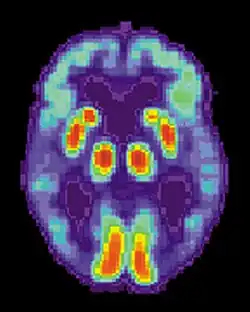

Kritéria pro diagnózu Alzheimerovy choroby stanovují dva hlavní dokumenty – DSM-5 (Diagnostic and Statistical Manual of Mental Disorders, edice 5) a NIA-AA (National Institute on Aging—Alzheimer’s Association Criteria). Hodnotí se přítomnost demence, nedostatečnosti v alespoň dvou kognitivních oblastech, pozvolný nástup a progresívní zhoršování stavu a dále je nutné vyloučit další možné příčiny demence. Diagnózu je možné podpořit také biochemickým vyšetřením mozkomíšního moku (snížená hladina rozpustného amyloidu Aβ42 a zvýšená hladina proteinu tau) a mozkovými zobrazovacími metodami, zejména pozitronovou emisní tomografií (PET) a magnetickou rezonancí (MRI).[2]